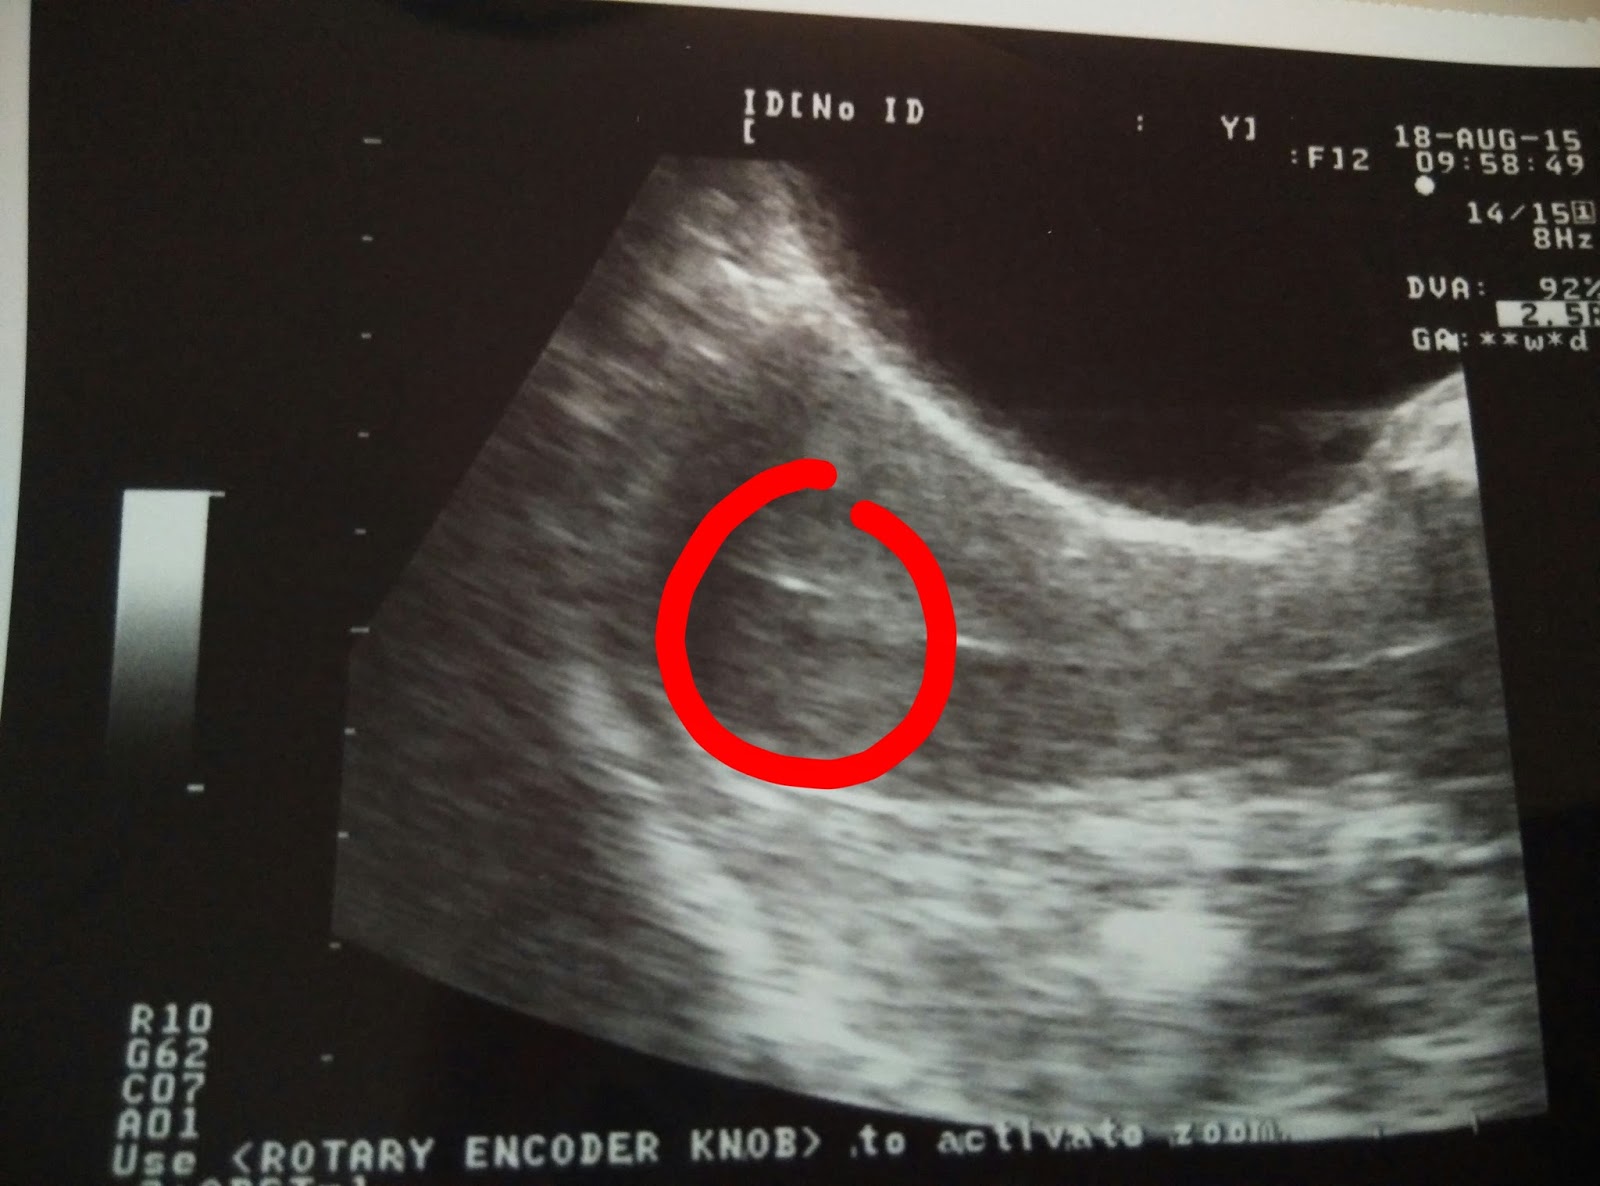

在等候的時間,姑娘給了我看胚胎的照片,

這兩個就是我的龍鳳胎了。

醫生叫我們先看上面的電視,可看到一會兒會放進去的兩個胚胎。

之後便可看前面的超聲波儀,可看到胚胎被放進去的情況。